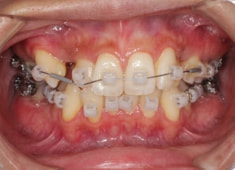

治療開始から24ヶ月後